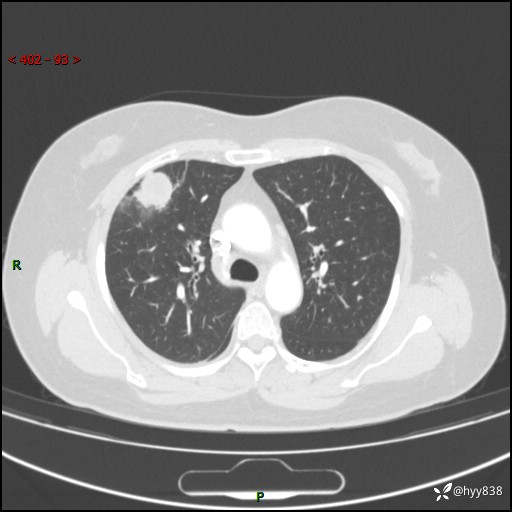

中年女性,间断胸痛2天。“又见”胸膜下团块,性质难定---结果公布~

现病史:患者于2天余前无明显出现间断胸痛,无头痛、头晕,无心慌、胸闷、胸痛、呼吸困难、低热、盗汗,无腹痛、腹胀等不适,未进行进一步诊治。于2024.04.14在当地市人民医院行胸部CT检查提示:右肺上叶胸膜下结节。现患者为求进一步诊治,来我院就诊。以“肺肿物”收入我科。 患者自起病以来,精神可,睡眠可,饮食可,大小便正常,体重无明显改变。

胸部CT增强(肺窗,外院平扫)